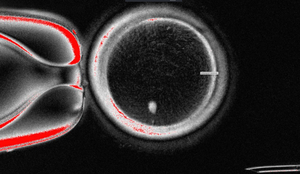

Những tế bào trứng được tạo từ kỹ thuật này tiếp tục được thụ tinh với tinh trùng trong môi trường phòng thí nghiệm. Một số trường hợp đã phát triển đến giai đoạn phôi nang – mốc đánh dấu sự hình thành phôi sớm, tương đương thời điểm có thể cấy ghép trong quy trình thụ tinh trong ống nghiệm (IVF).

Dù tỷ lệ thành công còn khiêm tốn – chỉ khoảng 9% trong tổng số 82 trứng nhân tạo phát triển tới giai đoạn phôi nang – nghiên cứu vẫn được xem là một bước tiến lớn. Đây là lần đầu tiên tế bào da người được chuyển đổi thành trứng có tiềm năng sinh sản thực sự. Thành tựu này đặt nền móng cho những kỹ thuật mới có thể vượt qua giới hạn tự nhiên về sinh sản.

Tuy nhiên, bên cạnh những điểm sáng, nghiên cứu cũng cho thấy không ít thách thức. Một trong những vấn đề lớn chính là sự xuất hiện của các bất thường về nhiễm sắc thể ở phần lớn các phôi tạo ra. Những sai lệch này làm dấy lên lo ngại về tính ổn định và an toàn sinh học của phương pháp mới. Ngoài ra, hiệu suất chuyển đổi thành công còn rất thấp, và đến nay chưa có phôi nào phát triển vượt quá giai đoạn phôi nang.